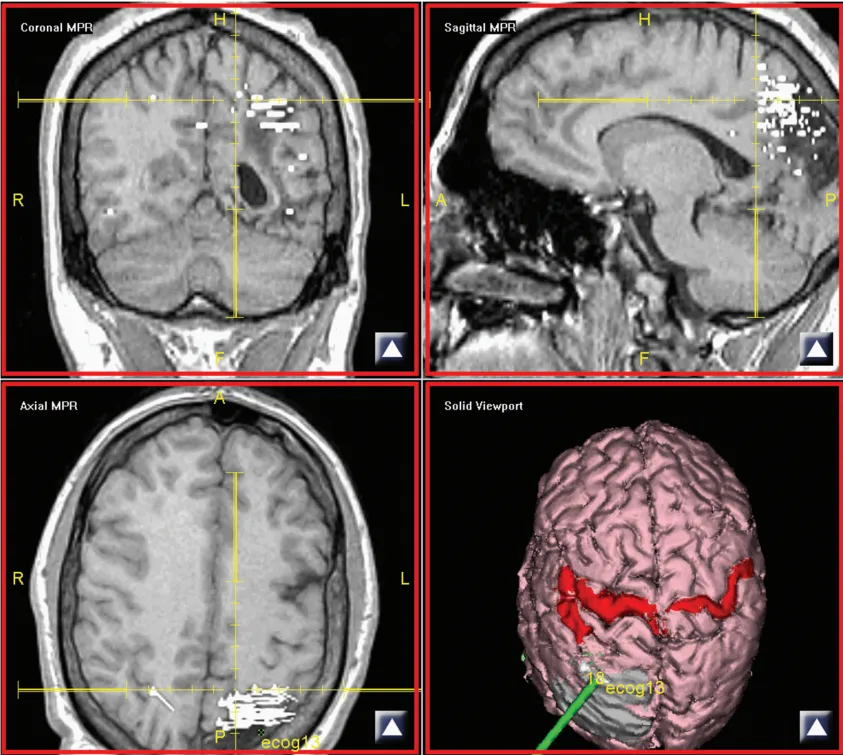

这项技术的中文名称很长,简写MEG。它的工作逻辑是捕捉大脑皮层神经元活动时产生的微弱磁场信号——这种信号比地球磁场弱上亿倍,必须依靠超导量子干涉仪才能探测到。临床操作中,MEG通常与磁共振成像(MRI)联合使用,生成一种叫磁源成像(MSI)的三维图像,将捕捉到的电活动叠加到患者的脑部解剖结构上,实现"所见即所在"的精准定位。

举个例子:左侧顶叶如果存在局灶性皮质发育不良,磁源成像中会以黄色点带橙色轮廓标注棘波源簇的位置;结合弥散张量成像(DTI)序列,蓝紫色的皮质脊髓束清晰可见,而最终手术切除的区域则用橙色区域标注。两者对照,外科医生在进入手术室前就已经有了完整的"作战地图"。